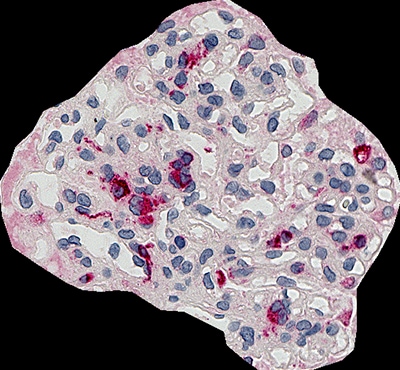

以下は、CD68(マクロファージ)の糸球体占有率を解析したものです。HE染色を行い、腎生検の全体像を撮影しています。通常、厚みのあるサンプルはピントが合いづらいですが、Zスタック撮影により全体にピントのあった顕微鏡観察が可能となっています。

糸球体の占有率 4.3 %